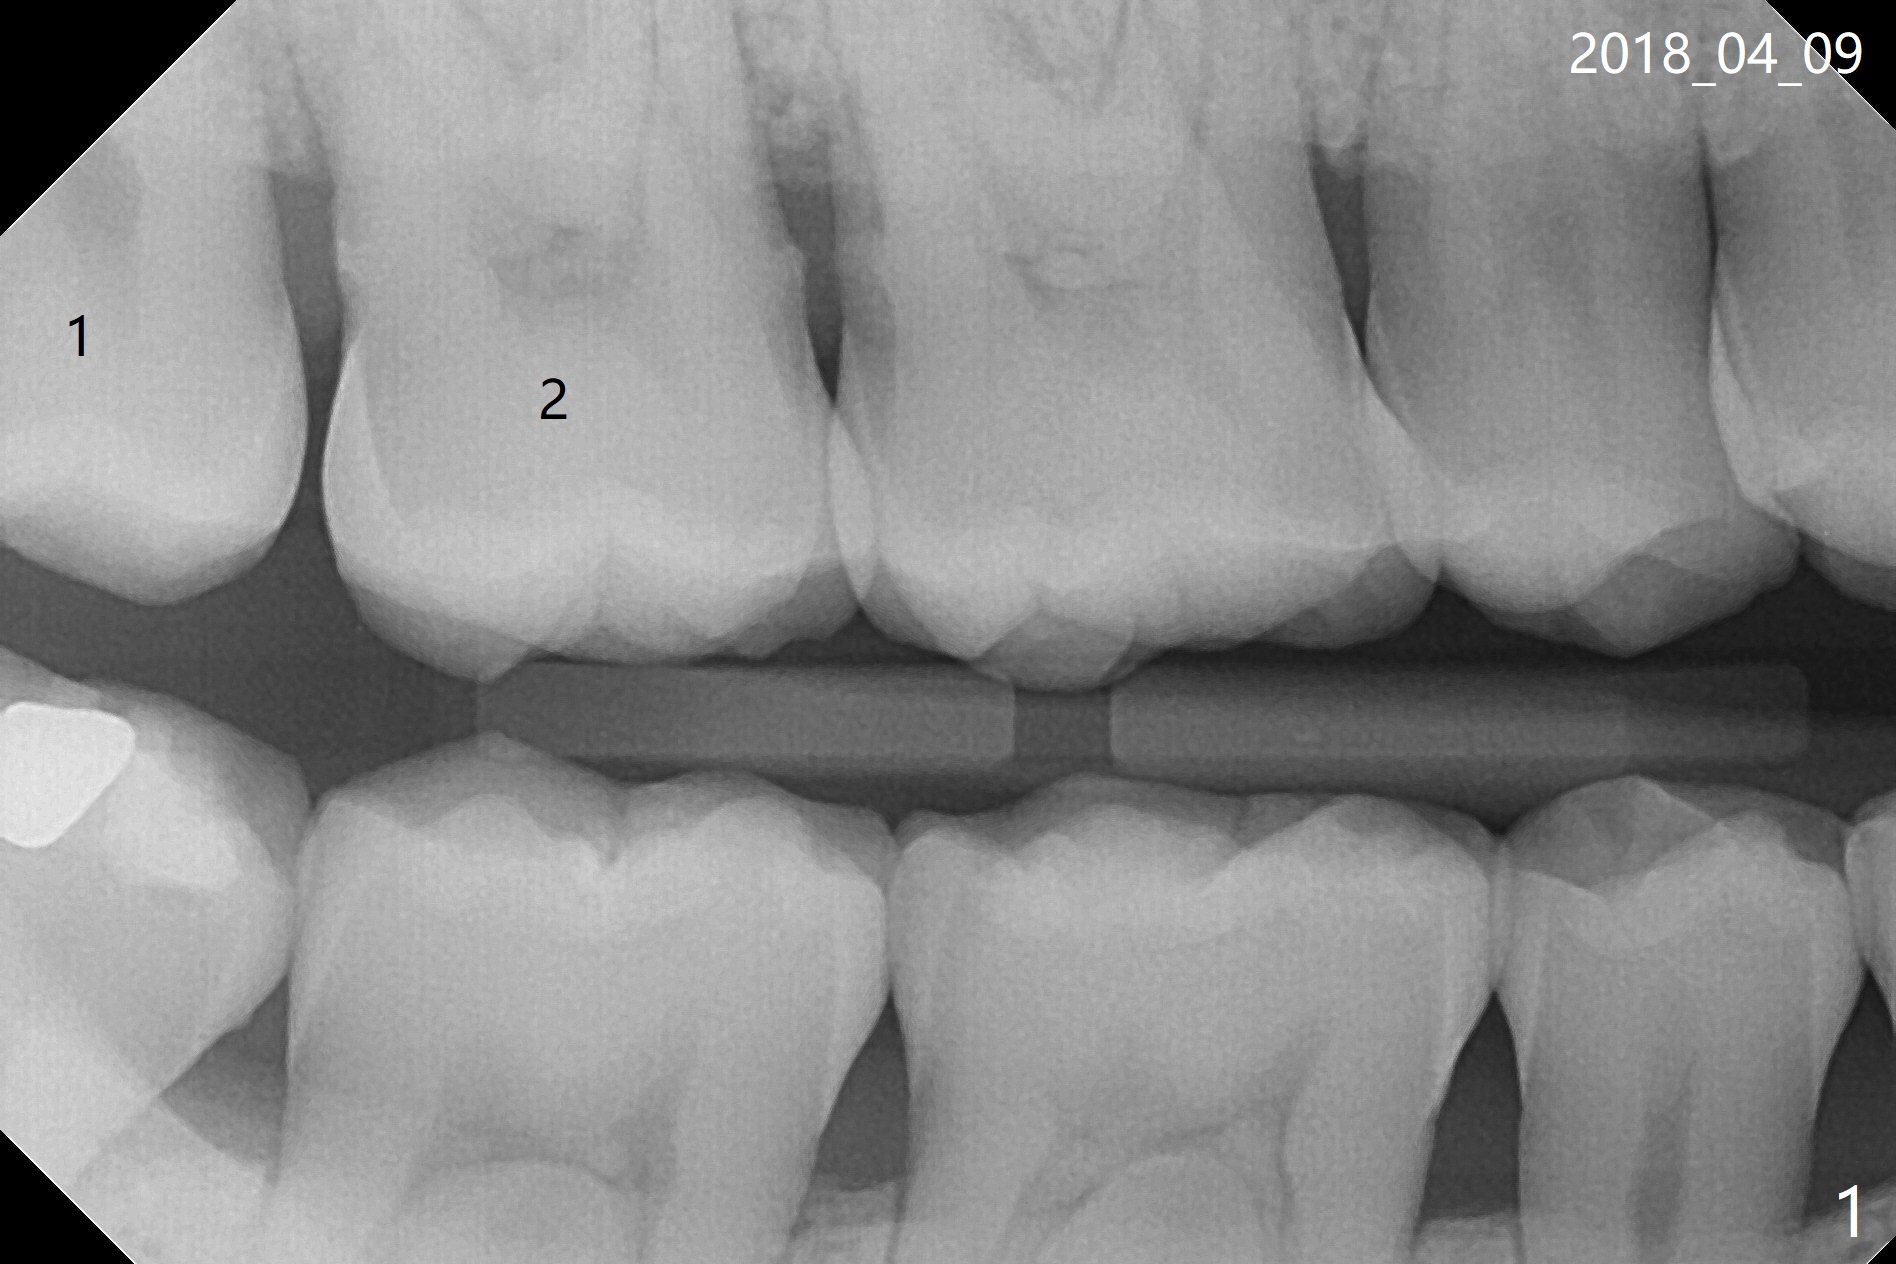

A 35-year-old woman requests extraction of the tooth #1 (food impaction between #1 and 2, Fig.1) and 16 (pain and 6 mm pockets between #15 and 16, Fig.2). In spite of the fact that there is bone loss between #14 and 15 (Fig.3), there is no deep pocket between them. After extraction of #16, SRP is performed in the distal surface of #15 with removal of granulation tissue and application of Endogain. Osteogen plug (Fig.4 O) is placed in the apical and distal portion of the socket of #16 (red dashed line), while allograft (G) against the distal root surface of #15. Finally Collagen plug (C) and 6-month membrane are placed in the opening of the socket, followed by suturing and periodontal dressing. The bone density is high post #1 extraction (Fig.6), related to difficult removal. It appears that bone graft at #16 (^) remains in place 15 months postop. Since no buccal trough is made for extraction, the external oblique ridge is present at #17 and 32 before and after surgery. Bond Apatite is placed with Collagen Plug (Fig.7).